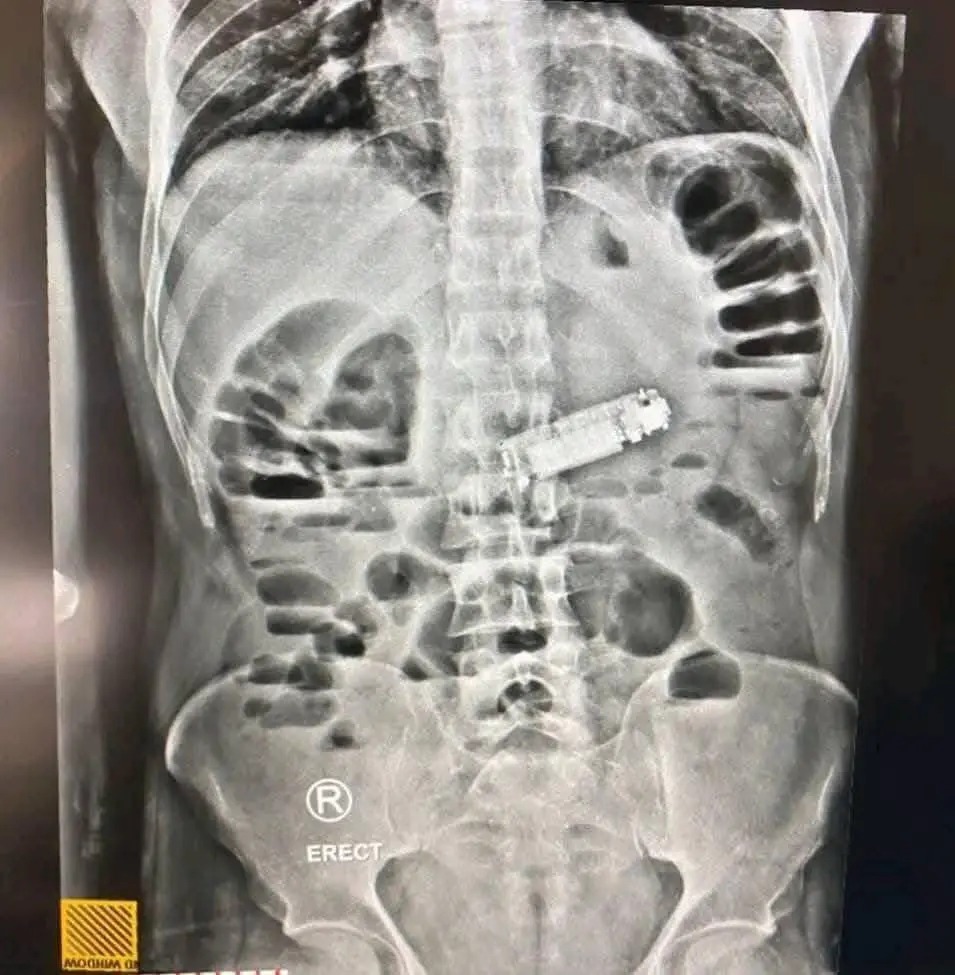

وبعد إجراء الفحوصات الشاملة، بما في ذلك الأشعة المقطعية والتحاليل الطبية، تبيّن وجود جسم غريب يسد فتحة البواب في المعدة، اتضح لاحقاً أنه هاتف محمول صغير الحجم، ما شكل خطراً كبيراً على حياة المريض.

وتمكن الفريق الطبي من استخراج الهاتف بنجاح دون التسبب بأي مضاعفات صحية خطيرة، في عملية وصفت بأنها "استثنائية ونادرة".